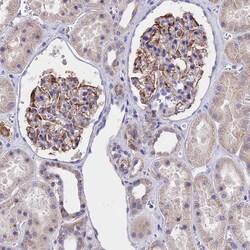

Immunogen sequence: KRTAVRLGDP HFYQDSLWLR KEFMQVRR Highest antigen sequence identity to the following orthologs: Mouse - 96%, Rat - 96%.

| Antigen | TMEM138 |

| Anwendungen | Immunohistochemistry (Paraffin), Western Blot |

| Gen | TMEM138 |

| Gen-Alias | HSPC196; HSPC198; JBTS16; TMEM138; Transmembrane protein 138 |